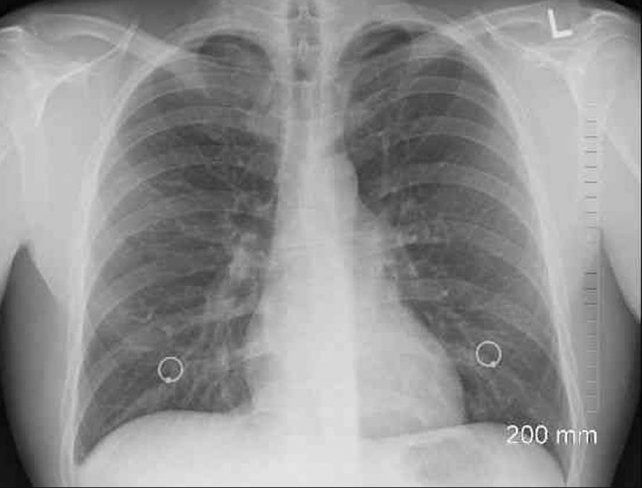

El cáncer de pulmón es la principal causa de muerte por cáncer a nivel mundial. Los dos tipos principales de cáncer de pulmón son de células pequeñas y de células no pequeñas.

El cáncer de pulmón de células no pequeñas (CPCNP) es uno de los tipos más comunes de cáncer de pulmón y representa hasta el 84% de los diagnósticos con tasas de sobrevida que varían según el estadio y el subtipo de cáncer cuando se diagnostica.

Para los pacientes diagnosticados con cáncer de pulmón metastásico, la tasa de sobrevida a cinco años es aproximadamente del 5%.